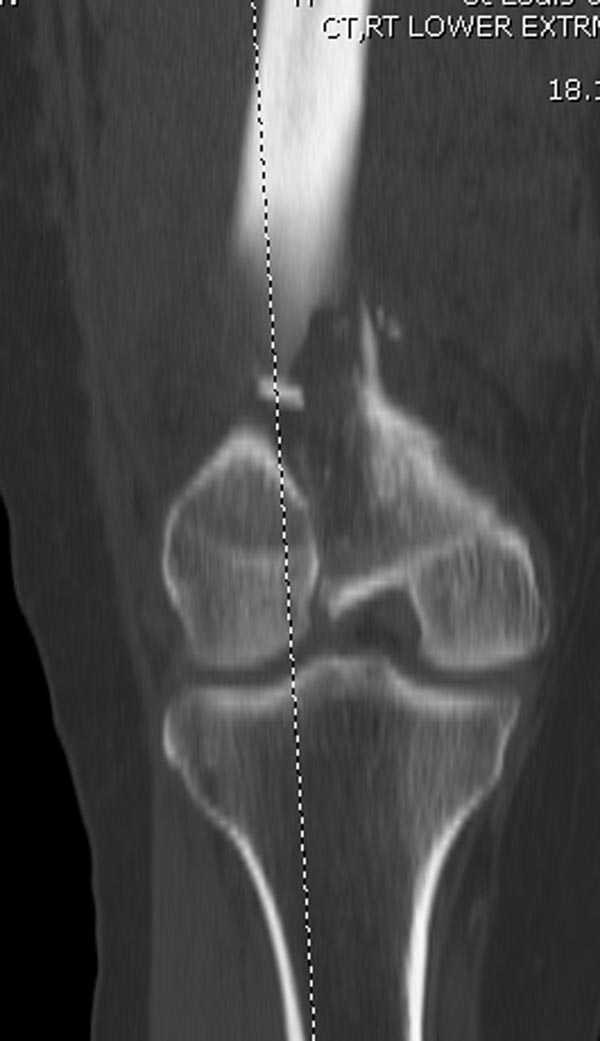

Это перелом не нижней трети, а дистального суставного конца, с распространением на диафиз. Что-то между C2 и C3. Но пока ближе к C2 по увиденному - вторую проекцию еще не показали.

На профиле стало видно, что открываться придется, это перелом C3, хотя можно назвать и C2+, т.е. с еще и фронтальным раскалыванием одного мыщелка. Надо сделать медиальную артротомию, ступеньку на внутреннем мыщелке устранить, ввести либо несколько временных спиц спереди назад, или сразу винт вдоль эллипса мыщелка. А дальше как выше написано - дистрактор, и штифтовать. Учитывая наличие открытого колена - вполне уместно ретроградно.